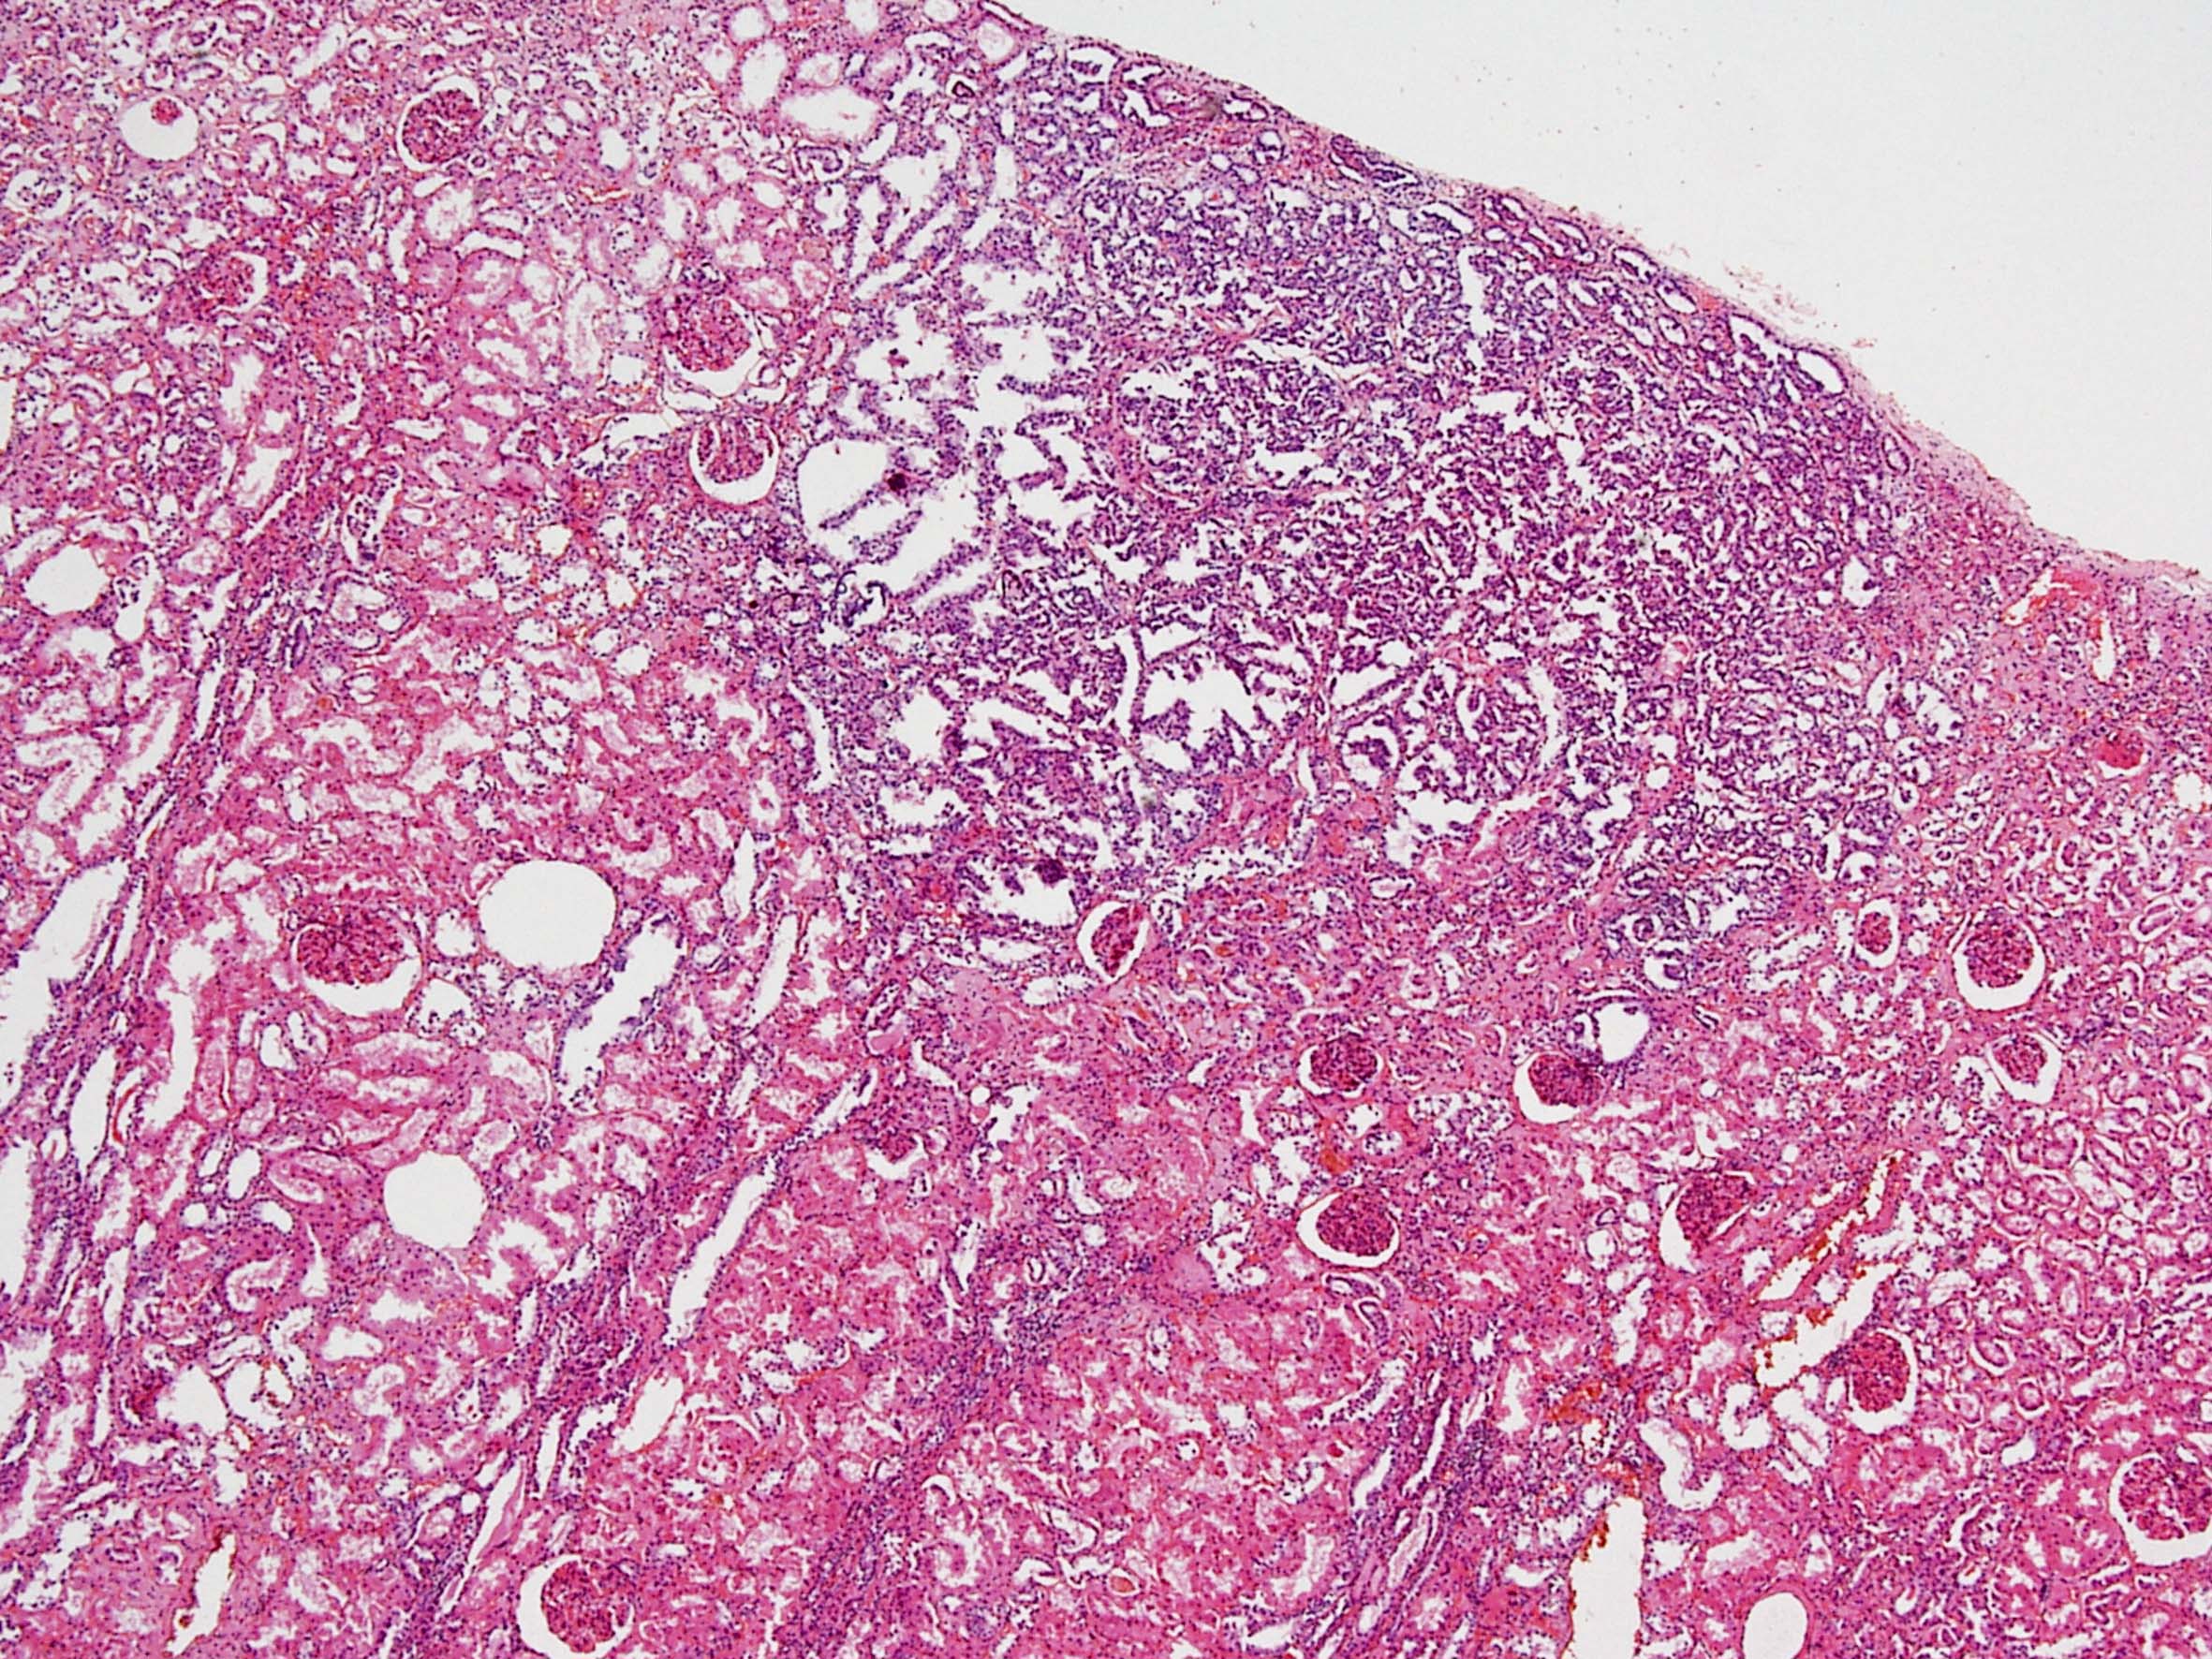

Classification of renal tumors

Case ID: 228